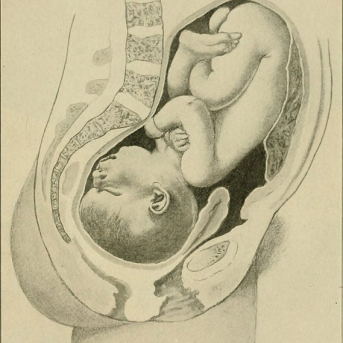

Na 36a semana é oficialmente quando entra no 9º mês de gestação, seu bebê está quase pronto para nascer. Além de continuar a ganhar peso, o foco agora é terminar de amadurecer os pulmões1 para que possa respirar tranquilamente logo após o nascimento. A respiração da mulher estará melhor nessa fase, mas as idas ao banheiro estarão ainda maiores, pois todo o peso agora esta sob a bexiga.

Chegar à 37a semana do nono mês da gravidez é motivo comemorar porque se o bebê nascer agora já não é mais considerado prematuro e nasce a termo. Iniciando essa semana, a penugem, ou lanugo2 como é conhecida, que envolvia todo seu corpo agora começa a cair. O vernix que protegia sua pele do líquido, onde ficou em total imersão tanto tempo, também desaparece dando lugar a traços mais fortes, covinhas e características próprias do bebê.

Estamos quase na reta final, na 38a semana de gestação, seu bebê agora já chega a pesar em média 3 kg, mas ainda continua a acumular gordura para conseguir suportar a temperatura de fora da barriga. Seu corpo esta em perfeito estado de funcionamento, inclusive seu cérebro e seus pulmões. O intestino também está pronto e o mecônio já está formado se preparando para ser expelido como o primeiro cocô do bebê, que ocorre normalmente logo após o nascimento.

Na 39a semana, o líquido amniótico3 que era uma água transparente e límpida agora se torna um liquido leitoso, pois todo o vertix contido na pele do bebê se soltou e se misturou ao líquido amniótico junto de resíduos da sua pele que vão se soltando. As visitas ao ginecologista agora são mais constantes para acompanhar o batimento cardíaco do bebê.

Enfim, 9 meses de gravidez completos, o terceira semestre termina e com a 40a semana chega em média a tão esperada hora.. Seu bebê está realmente pronto para vir ao mundo e você pode entrar em trabalho de parto a qualquer momento, portanto esteja preparada. O coração do pequeno bate rápido com uma frequência de 110 a 160 vezes por minuto e durante o exame de cardiotoco será possível acompanhar. Fique atento a sinais como endurecimento da barriga, cólicas e diarreia pois são sinais que seu trabalho de parto está iniciando.